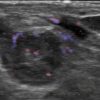

Ung thư vú

» Thông tin: Nữ giới – 69 tuổi.

» Lâm sàng: Kiểm tra sức khỏe.